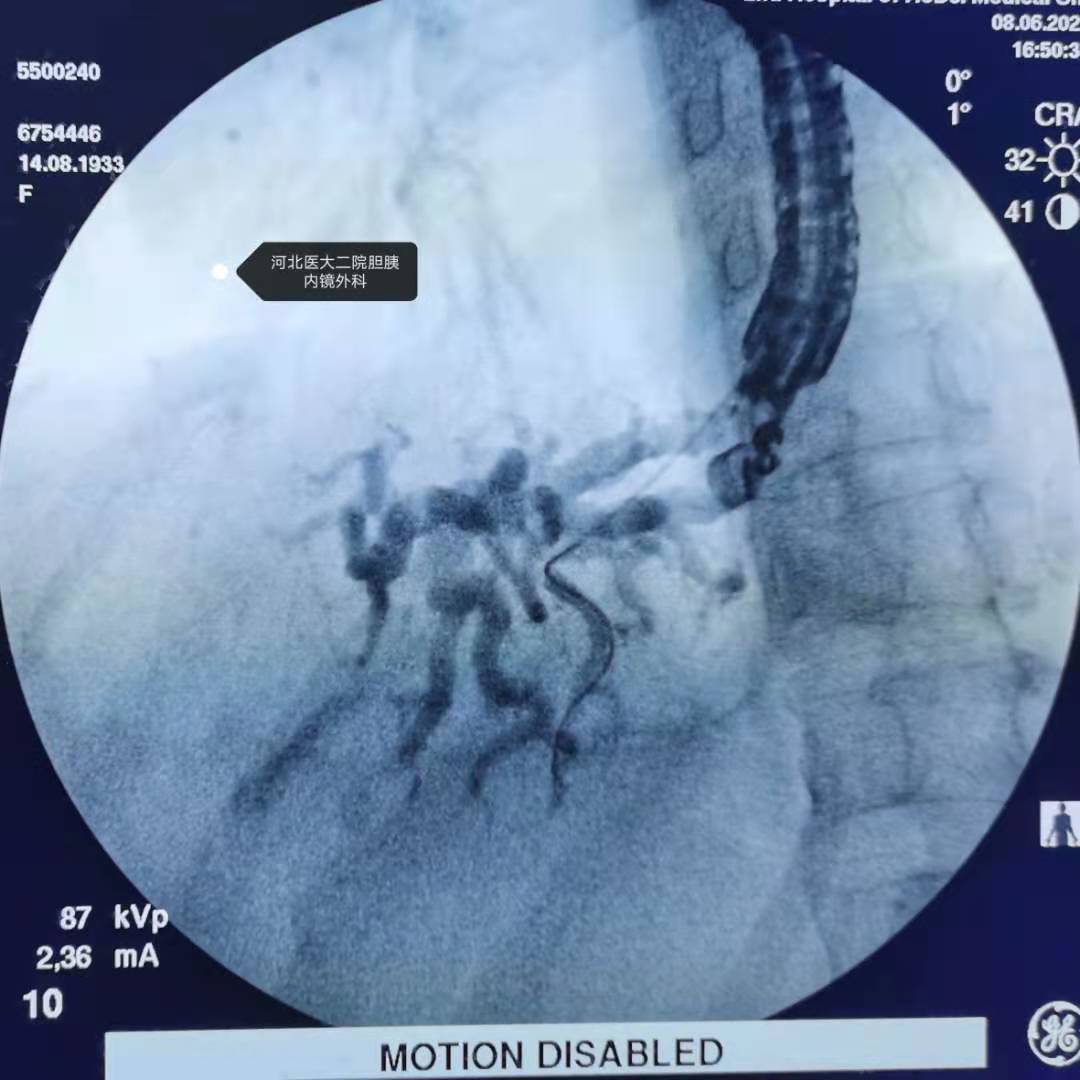

造影。

进入导丝。

导丝去了胆管上游,再来。